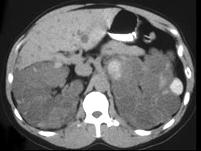

女,52岁,腰部酸胀,根据影像图像,判断其最可能的诊断 ( )A、肾脓肿B、肾盂癌伴出血C、肾细胞癌D、多囊肾E、多房性肾囊肿

问题 女,52岁,腰部酸胀,根据影像图像,判断其最可能的诊断 ( )

选项 A、肾脓肿 B、肾盂癌伴出血 C、肾细胞癌 D、多囊肾 E、多房性肾囊肿

答案 D